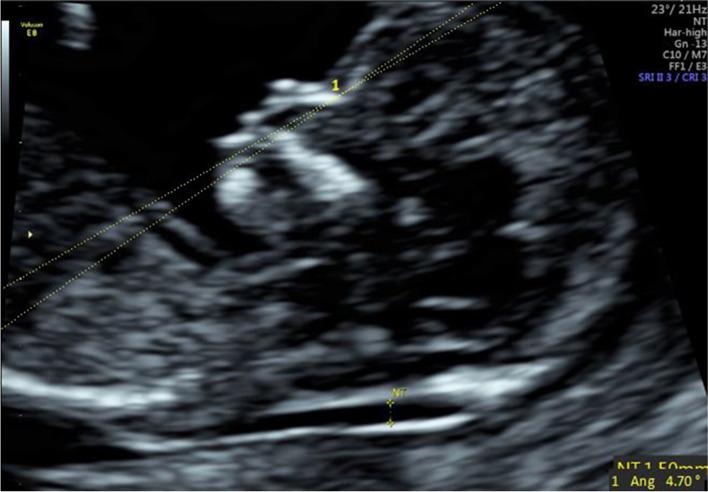

To study the correlations between facial profile markers and crown-lump length (CRL) in a Chinese population, and to evaluate the clinical value of these markers for abnormal fetuses during the first trimester (11 to 13 gestational weeks).  METHODS: The facial profile markers were as followings: inferior facial angle (IFA), maxilla-nasion-mandible (MNM) angle, facial maxillary angle (FMA), frontal space (FS) distance and profile line (PL) distance. These markers were measured in facial mid-sagittal section through ViewPoint 6 software. The diagnostic value of these markers for abnormal fetuses was assessed by receiver operating characteristic (ROC) curves.

According to the first-trimester scanning (FTS) and follow-up, 31 fetuses were enrolled in the abnormal group, including 14 cases of trisomy 21, 7 cases of trisomy 18, 10 cases with cleft lip and palate (CLP), and 1000 normal fetuses were selected. Among the normal fetuses, the IFA, FS distance and PL distance had negative correlations with CRL. The MNM angle and FMA had positive correlations with CRL. The mean IFA values for fetuses with trisomy 21 and trisomy 18 were 74.11° (standard deviation (SD) 7.48) and 69.88° (SD 7.08), respectively, which were significantly smaller than the normal fetuses (p = 0.013; p = 0.003). The mean MNM angle of fetuses with trisomy 18 and CLP were 6.98° (SD 2.61) and 9.41° (SD 2.57), respectively, which were significantly greater than the normal fetuses (p = 0.005; p < 0.001). The mean FMA values of trisomy 18 fetuses were 63.95° (SD 4.77), which was significantly smaller than the normal fetuses (p < 0.001). The mean FS distance of CLP fetuses was -0.22 mm (SD 1.38), which was significantly smaller than the normal fetuses (p < 0.001). The mean PL distance of trisomy 21, trisomy 18 and CLP fetuses were 2.89 mm (SD 0.41), 2.91 mm (SD 0.56) and 2.71 mm (SD 0.37), respectively. The difference with the normal fetuses had no statistical significance (p = 0.56; p = 0.607; p = 0.54).

面部轮廓标志如下:下面部角(IFA)、上颌-鼻根-下颌(MNM)角、面上部角(FMA)、额面间距(FS)和轮廓线(PL)距离。通过 ViewPoint 6 软件在面部正中矢状面测量这些标志。通过受试者工作特征(ROC)曲线评估这些标志对异常胎儿的诊断价值。

根据孕早期扫描(FTS)和随访,31 例胎儿被纳入异常组,包括 14 例 21 三体,7 例 18 三体,10 例唇腭裂(CLP),1000 例正常胎儿。在正常胎儿中,IFA、FS 距离和 PL 距离与 CRL 呈负相关。MNM 角和 FMA 与 CRL 呈正相关。21 三体和 18 三体胎儿的 IFA 平均值分别为 74.11°(标准差(SD)7.48)和 69.88°(SD 7.08),显著小于正常胎儿(p=0.013;p=0.003)。18 三体和 CLP 胎儿的 MNM 角平均值分别为 6.98°(SD 2.61)和 9.41°(SD 2.57),显著大于正常胎儿(p=0.005;p<0.001)。18 三体胎儿的 FMA 平均值为 63.95°(SD 4.77),显著小于正常胎儿(p<0.001)。CLP 胎儿的 FS 距离平均值为-0.22mm(SD 1.38),显著小于正常胎儿(p<0.001)。21 三体、18 三体和 CLP 胎儿的 PL 距离平均值分别为 2.89mm(SD 0.41)、2.91mm(SD 0.56)和 2.71mm(SD 0.37),与正常胎儿相比差异无统计学意义(p=0.56;p=0.607;p=0.54)。